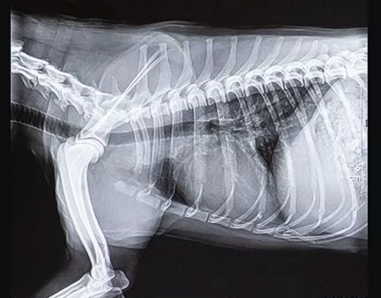

寵物dr拍攝效果圖

2、寵物專用平板。傳統(tǒng)的平板探測器,相當(dāng)于普通攝像機(jī),對于拍攝急促呼吸狀態(tài)下的寵物,成像效果存在著明顯缺陷,而目前寵物dr使用的平板,則可以清晰的記錄動(dòng)物的精準(zhǔn)瞬間。